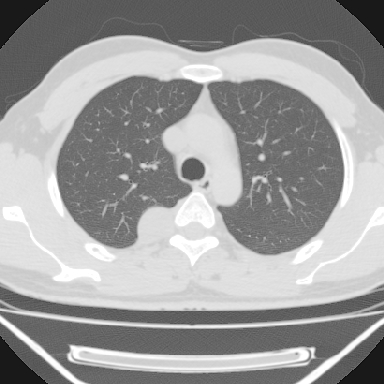

右上后纵隔旁软组织肿块影,与肺界面光滑,与胸壁呈钝角相交,提示肺外病变。位于肋骨下缘,边缘清楚,呈三角样指向与右侧椎间孔,但并示进入椎间孔;与对侧神经根对比,属同一走行方向。

考虑后纵膈良性肿瘤,神经源性肿瘤可能大。

鉴别:胸膜来源肿瘤。影像表现虽有肺外征象,但无胸水等相应佐证;再者,病史前10年,超长,与胸膜肿瘤不太吻合。

建议:再次查体,问清疼痛部位,如为1~2个肋间痛则神经源性肿瘤可能大,如疼痛较弥散,不按肋间分布,则可能为后纵膈其它来源肿瘤。